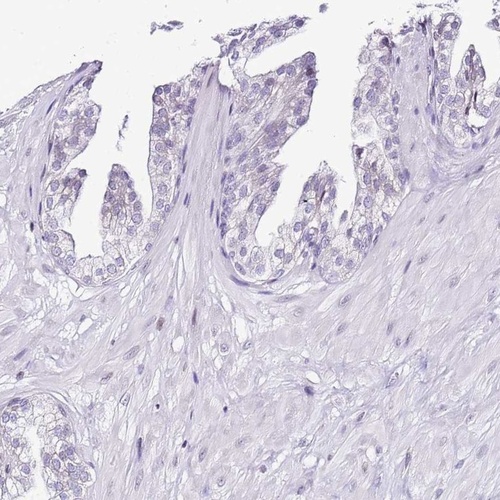

Immunohistochemistry analysis in human cervix, uterine and prostate tissues using Anti-PRR15 antibody. Corresponding PRR15 RNA-seq data are presented for the same tissues.